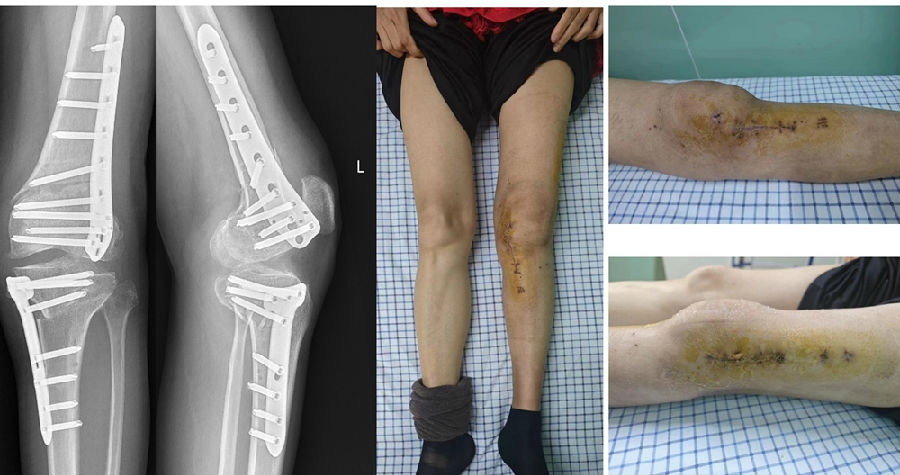

术后X线片

术后1个月

对于同时存在股骨和胫骨较大畸形的患者,建议同时行DFO+HTO双截骨,中短期临床疗效良好。可在恢复下肢机械轴线的同时纠正关节线的倾斜;还能避免单纯股骨侧或胫骨侧大角度矫正下肢畸形。

掌握技术,术前精确计划:冠状位&矢状位;术中规范操作:合页完整,中立位力线。